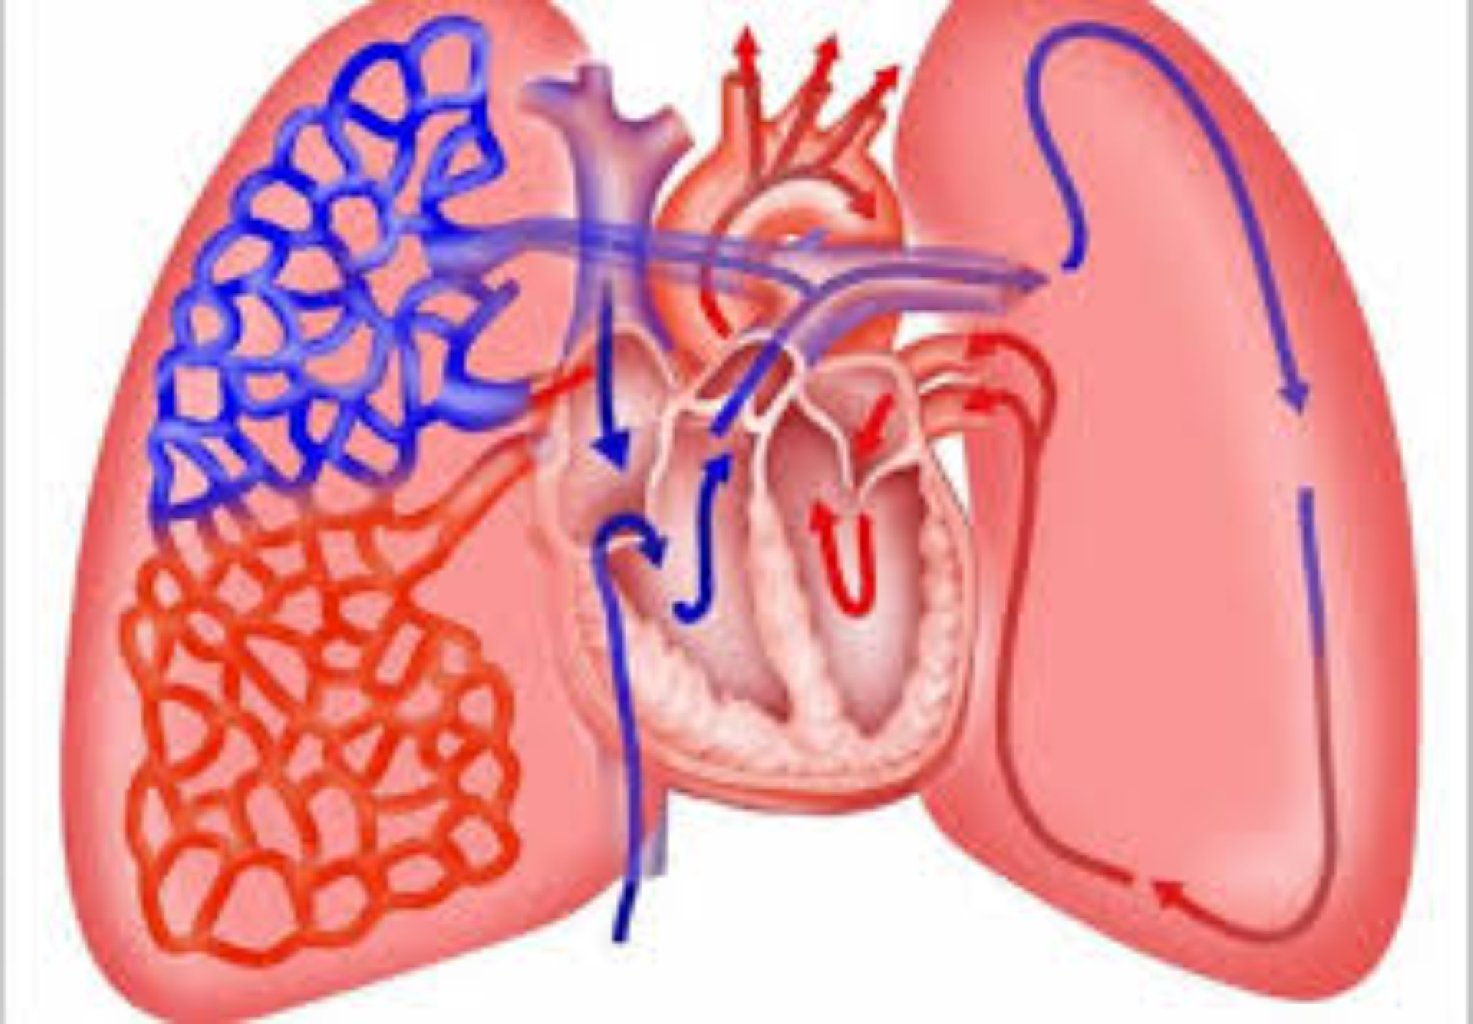

Ağciyər emboliyasının ən çox görülən səbəbi ayaq damarlarında meydana gələn dərin ven trombozu (DVT) ...

Səbəblər: Uzun müddət hərəkətsiz qalmaq (məsələn, uzun müddətli uçuşlar və ya yataq istirahəti) ...